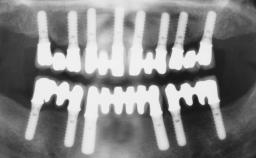

Conventional Loading of Eight Implants in the Maxilla and Final Restoration with a Full-Arch Gold-Ceramic FDP

A 35-year-old Caucasian female presenting with advanced periodontal disease involving both the maxillary and the mandibular dentition was referred for evaluation. The patient, a non-smoker in good general health, requested treatment for recurrent periodontal abscesses, tooth mobility, and discomfort during chewing, as well as restoration of her missing teeth with a fixed prosthesis to improve mastication and esthetics. All residual maxillary teeth exhibited plaque deposits, deep pockets, bleeding on probing, and class III mobility and were evaluated as hopeless. All residual mandibular teeth except tooth 37 could be maintained after periodontal therapy.

# of Implants 8

Type of Implants One-Piece

Prosthesis Type FDP

Defining Characteristics Fully edentulous upper jaw to be rehabilitated with four or more implants

Modality Fixed hybrid bridge on 5+ implants

Defining Characteristics Fully edentulous upper jaw to be rehabilitated with an implant-borne fixed dental prosthesis

Loading Protocol Conventional or early